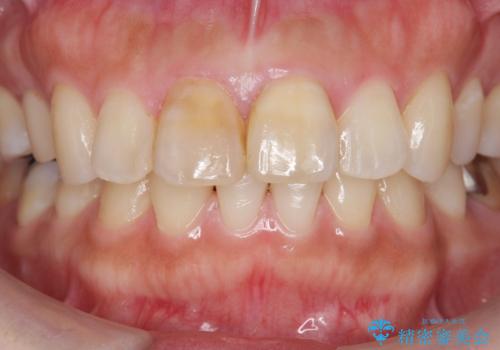

- 歯の神経を除去したのちの、変色の改善を希望され来院されました。

再度根管治療を行ったのちの、オールセラミッククラン治療を計画します。

色調の再現に優れるオールセラミッククラウン スペシャルプランでの治療を希望されました。(保証5年間)